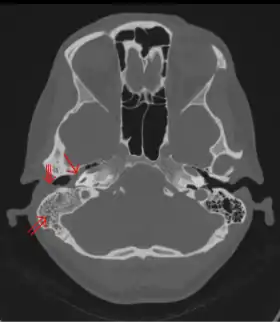

Tomodensitométrie: Otite moyenne (flèche simple) et mastoïdite (flèche double) du côté droit (côté gauche de l'image). Le conduit auditif externe est partiellement occupé par la suppuration (flèche triple). Femme de 44 ans.